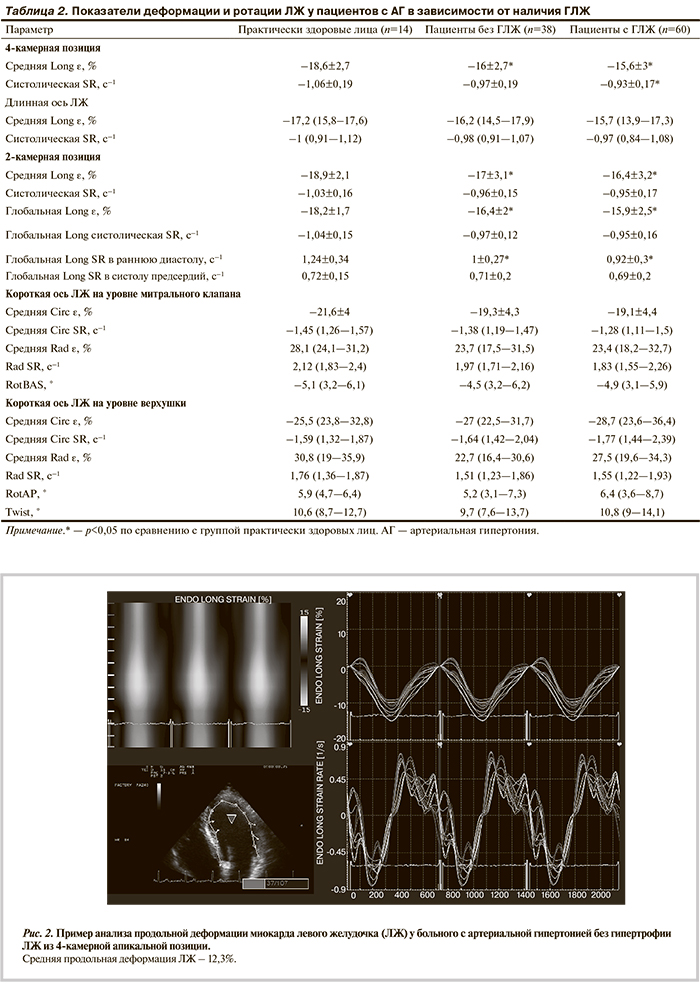

Показатели деформации и ротации ЛЖ при АГ в зависимости от наличия ГЛЖ. Глобальная продольная ε была статистически значимо снижена у пациентов без ГЛЖ по сравнению с таковой у практически здоровых лиц (табл. 2). Сегментарный анализ продемонстрировал соответствие закономерностям, выявленным для всей когорты пациентов (рис. 2). Показатели циркулярной и радиальной ε и SR достоверно не отличались от значений у здоровых лиц. Параметры вращения и скручивания ЛЖ также не изменялись.

Таким образом, у мужчин без ГЛЖ наблюдается снижение продольной деформации ЛЖ, что позволяет рассматривать это ранним признаком поражения миокарда при АГ.